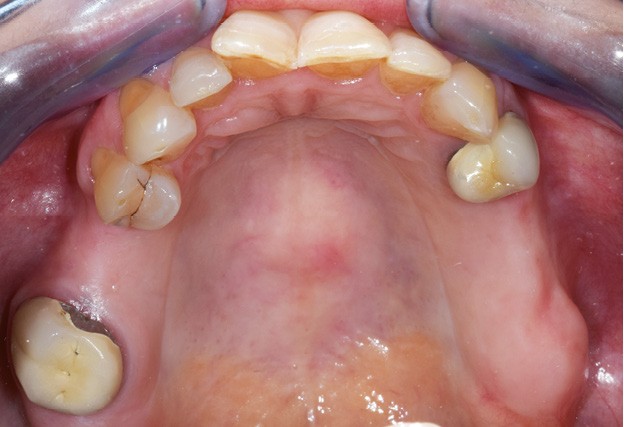

Nous sommes en présence, au maxillaire, d’un édentement de classe 2 subdivision 1 de moyenne étendue (fig. 3). La problématique propre à ce cas de classe 2 est le soulèvement lors de la mastication d’aliments mous/collants et l’asymétrie. Cependant, la présence d’une subdivision compense en partie l’asymétrie. La recherche d’appuis les plus antérieurs possible à l’axe de rotation pour contrer le mouvement de soulèvement postérieur est également…